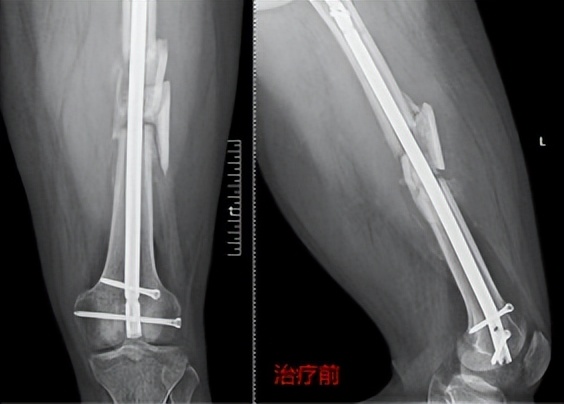

骨干骨折术后骨不愈合

患者袁某,男,22岁,正值风华正茂的年龄,不幸的是1年前因车祸致左股骨干粉碎性骨折,在当地医院行切开复位髓内钉内固定术,术后伤口愈合良好,患者满怀希望疾病早点康复,早点回学校读书,但随着术后的每一次复查,都是一次次的打击,因为每次复查都没有发现骨折愈合迹象,且在术后一年的时候出现了更不好的是股骨髓内钉近端锁定钉断裂,到省级多家医院求医,给的治疗方案都是手术植骨治疗,患者及家人都十分焦急,经多方打听,慕名来到郑州市骨科医院骨病·骨肿瘤科I找到王顺利主任,王主任详细询问病史及阅片后,告诉患者可以行骨伤病最新绿色疗法冲击波保守治疗,不用手术植骨治疗,并为患者制定了个性化治疗方案,袁某非常高兴并满怀信心告诉王主任一定配合治疗,经过三个疗程的冲击波治疗股骨干骨折愈合了。